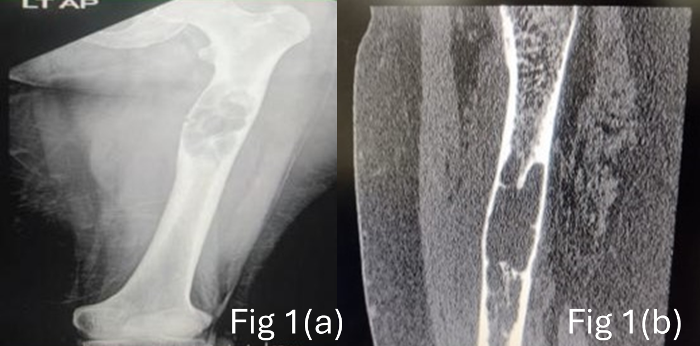

X ray left thigh

showed a lytic lesion in upper 1/3rd of left femur

with unicortical pathological fracture (Fig 1a).

The CT angiogram and MRI showed an expansile lytic

| Figure

1(a): X-ray showing lytic lesion in upper

1/3rd of left femur with unicortical

pathological fracture (b) CT Angiogram

-Well defined, lobulated, eccentrically

located lytic lesion in diaphysis of left

femur measuring 23 x 27 x 88 m with

cortical destruction. |